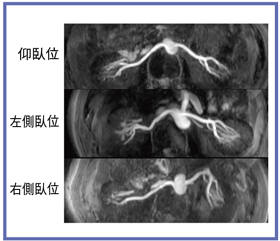

術前の画像検査は仰臥位で行われるため,手術の際の体位の違いによる乖離が問題となっていた。Titan 3Tの71cmオープンボアによって,仰臥位と左右側臥位で撮像を行い,腎臓および腎血管の移動・偏位を比較してみた(図5)。腎動脈は,大動脈からの分岐角が仰臥位と側臥位では大きく変わっていることが観察できる(図6)。また,腎臓も同様に,側臥位で上となる側の腎が,腹側へ偏位していた(図7)。

![]() 図6 検査体位による腎血管の移動 |